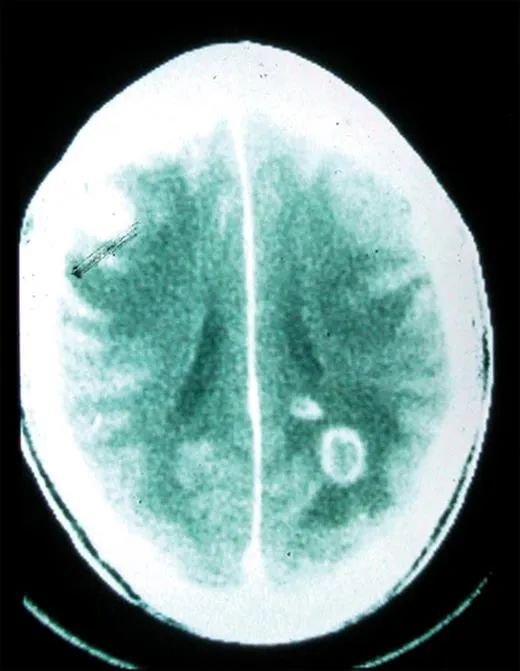

对于大多数免疫力正常的人类,感染了弓形虫后不会出现明显的病症。但对于免疫系统功能较弱的人来说,弓形虫则可能引起不同程度的症状,比如让人出现严重的眼部病变或神经系统症状。

人体内原本存在一些屏障,将人体重要部位与身体其他部分的内环境分割开来,防止病原体的入侵,但弓形虫却能够跨越这些屏障。例如,它们就能跨越血胎屏障,这就是为何如果孕妇感染了弓形虫,可能对胎儿造成严重的影响,严重时甚至可能导致流产;它们也能跨越血脑屏障,并引起各种中枢神经病症,比如癫痫等。当然,它们也能跨越血睾屏障,对男性的生殖系统产生影响。